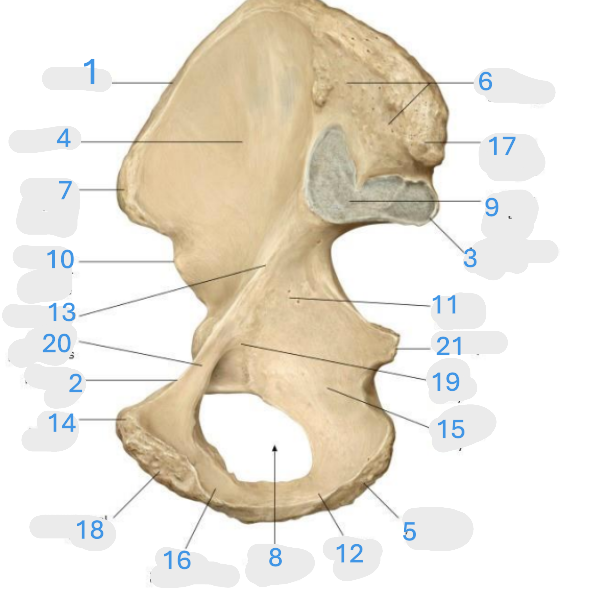

Where is the iliac crest

1

Where is the pectineal line

2

Where is the posterior iliac spine

3

Where is the iliac fossa

4

Where is the ischial tuberosity

5

Where is the iliac tuberosity

6

Where is the anterior superior iliac spine

7

Where is the obturator foramen

8

Where is the auricular surface of the ilium

9

Where is the anterior inferior iliac spine

10

Where is the ilium body

11

Where is the ischial ramus

12

Where is the arcuate line

13

Where is the pubic tubercle

14

Where is the ischium body

15

Where is the inferior pubic ramus

16

Posterior superior iliac spine

17

Where is the symphyseal surface

18

Where is the pubis body

19

Where is the superior pubic ramus

20

Where is the ischium body

21